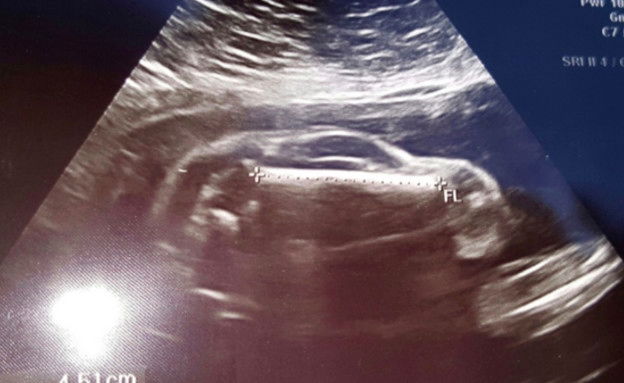

תמונות אולטרסאונד יכולות לחשוף את העוברים במגוון מצבים משעשעים, מרתקים, שגרתיים וחלילה מדאיגים. אבל התמונה הבאה גרמה לזוג רנה ומייק רוברטוס ממיזורי, ארה"ב, לחטוף הלם קל.

במקום תינוק בשלב התפתחותי כזה או אחר, נגלה לעיניהם...רכב. ולא סתם רכב, אלא אחד מדגם משפחתי רחב ומרווח.

למרות ההלם, האב לא התבלבל ומיהר לתעד את המראה המוזר ולהעלות אותה באתר רדיט - רשת חברתית פופולרית עם הכיתוב "אשתי בהיריון עם מכונית", ומשם התמונה הפכה לוויראלית ברחבי הרשת.

מצליחים למצוא את התינוק בתמונה?